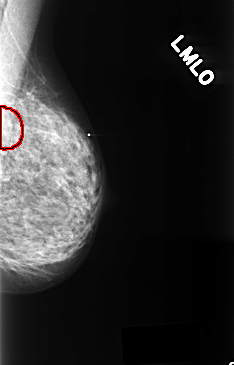

ics_version 1.0 filename C-0396-1 DATE_OF_STUDY 29 11 1996 PATIENT_AGE 68 FILM FILM_TYPE REGULAR DENSITY 3 DATE_DIGITIZED 13 10 1998 DIGITIZER LUMISYS LASER SEQUENCE LEFT_CC LINES 4376 PIXELS_PER_LINE 2864 BITS_PER_PIXEL 12 RESOLUTION 50 OVERLAY LEFT_MLO LINES 4376 PIXELS_PER_LINE 2808 BITS_PER_PIXEL 12 RESOLUTION 50 OVERLAY RIGHT_CC LINES 4392 PIXELS_PER_LINE 2760 BITS_PER_PIXEL 12 RESOLUTION 50 NON_OVERLAY RIGHT_MLO LINES 4392 PIXELS_PER_LINE 2808 BITS_PER_PIXEL 12 RESOLUTION 50 NON_OVERLAY |

FILE: C_0396_1.LEFT_MLO.OVERLAY TOTAL_ABNORMALITIES 1 ABNORMALITY 1 LESION_TYPE MASS SHAPE FOCAL_ASYMMETRIC_DENSITY MARGINS ILL_DEFINED ASSESSMENT 3 SUBTLETY 1 PATHOLOGY BENIGN TOTAL_OUTLINES 1 BOUNDARY |